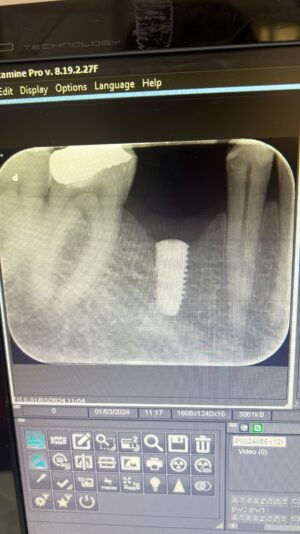

• Hello everyone,

These are osstem bone level implants which i placed 3 months ago. Upper right first premolar was immediate after extraction with grafting in the gap. 3 months after you can see some slight bone loss especially mesially of the upper premolar implant, would like to know the cause and how to prevent this? Also if implants are…

Read more

• For the upper pre-molar, potentially, it may not have been deep enough. The x-ray does look like it could’ve been deep enough, but if there was some buccal or Palatal bone loss on the mesial then it may had to have been slightly deeper to compensate for that and if there’s too much bone loss on either of those walls, it would definitely be…

• Another thing to consider is the proximity to the tooth anterior tooth. Did the anterior teeth have any perio-disease? Studies show that disease from neighboring teeth can extend up to 2mm outwards. This might be something to consider. Thanks for sharing!